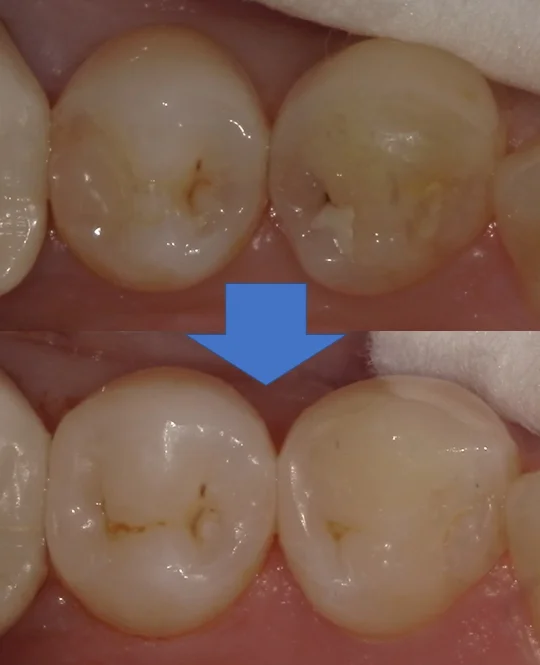

そして詰め終わったのがこちらです。

違和感なく綺麗に仕上げられたかと思います。

最近研磨の手法を切り替えたのですが、ツヤが良く出るようになって更に自然になるようになってきましたね。

術前術後の写真がこちらです。

適合も見栄えも違和感なく綺麗に仕上げられたかと思いますヽ(゚∀゚)ノ パッ☆